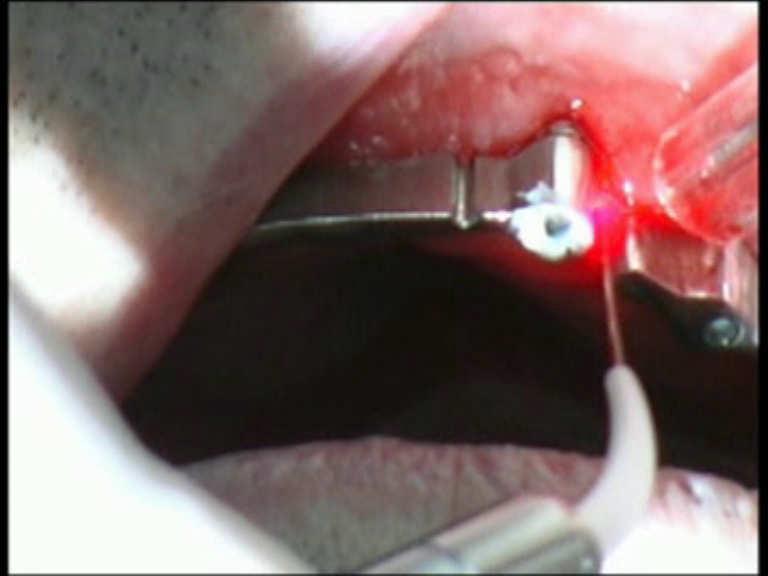

Peri-implantitis

Peri-implantitis is a dental term used to describe the destructive inflammatory process affecting the soft and hard tissues surrounding dental implants. The array of periodontal pathogens found around failing implants (those affected by peri-implantitis) are very similar to those found in association with various forms of periodontal disease.

Diode Laser 810nm

Power: 2.5 Watt,

pulsed 50 Hz

Time On/Off 10ms

Fibre 400 micron